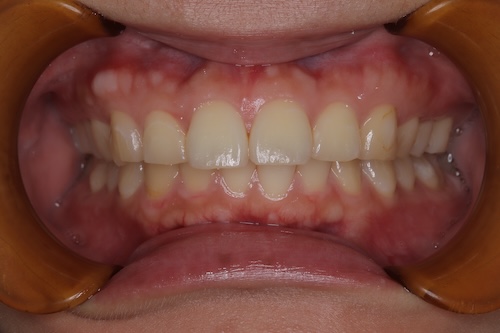

ホワイトニング症例報告

東京 ホワイトニングサロンボーテ神田の症例報告主訴2ヶ月後に挙式をするので、白くしたい

シェードの変化

右上1 A1からBL4

右下3 A3からC1

右上1 B1からBL4

右下3 C1からD2

シェードご満足いただき、メンテへ。

上下の色の差は残りますが、ご本人様ご満足いただけたのでメンテに移行した。